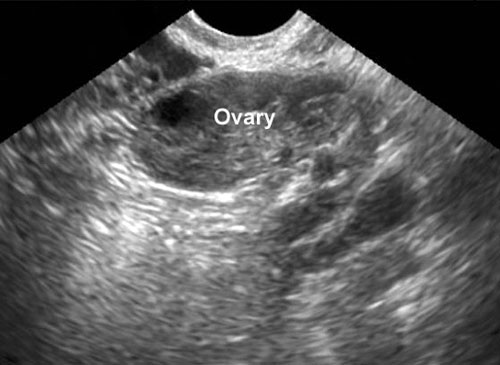

They took us into the operating room, put me up on the table and Ryan into the chair beside me. A window opened up and an embryologist in the back room asked us to look at the big screen to verify my name and birthday on the petri dish. When we looked up there, we could see the two blastocysts floating on the media and I thought that was the coolest part. The doctor visualized my uterine lining on the ultrasound, practiced putting a cath in, and then yelled "Load 'em up." After what seemed like an eternity with me laying on the table spread eagle with a speculum in, in came the tube that contained our babies. They inserted it, watched via ultrasound to ensure they knew it was at the back of the uterus, and then pushed the trigger and injected them in.